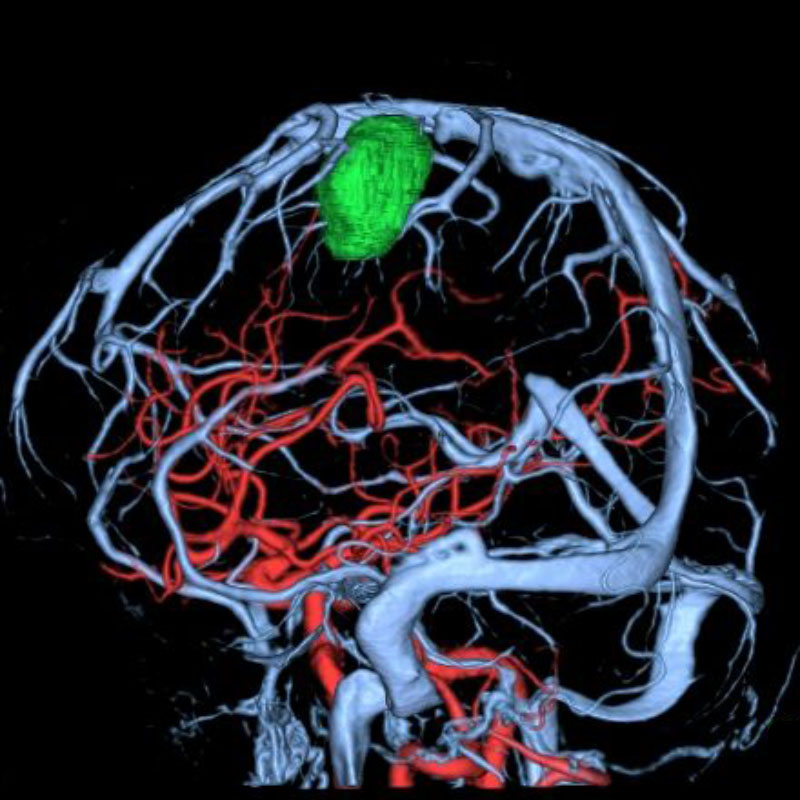

脳動静脈奇形

血管塞栓術

松田/濵田/元永